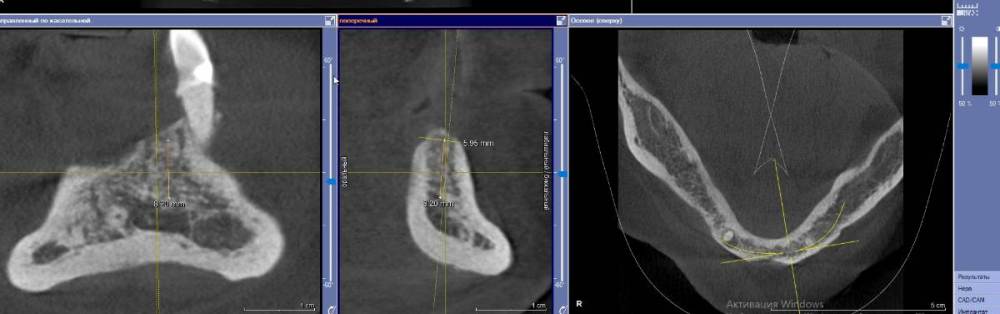

It'sGeorgy Опубликовано 3 февраля, 2022 Поделиться Опубликовано 3 февраля, 2022 (изменено) Коллеги, подскажите, с чем может быть связано такое настолько серьезное искажение на ОПТГ? 2 месяца думал, что завалил 1.5 в другую сторону, а на новом КТ оказалось все правильно. Скрытый текст Изменено 3 февраля, 2022 пользователем It'sGeorgy Ссылка на комментарий

kamranchick Опубликовано 3 февраля, 2022 Поделиться Опубликовано 3 февраля, 2022 лучше всего прицельник с позиционером, что оптг что кт не дают точной картинки, тем более штрауманн фонит будь здоров Ссылка на комментарий

It'sGeorgy Опубликовано 3 февраля, 2022 Поделиться Опубликовано 3 февраля, 2022 @kamranchick да, согласен, что лучше локсима + прицела после установки нет ничего. Но когда винтов много - просадка по времени получается, плюс асси с прицелом не всегда дружат. Но вышеуказанная ОПТГ дала повод задуматься целесообразности её в целом, если там настолько искажать может. 27 минут назад, kamranchick сказал: тем более штрауманн фонит будь здоров А разные винты с разной интенсивностью фонят? Не знал. Ссылка на комментарий